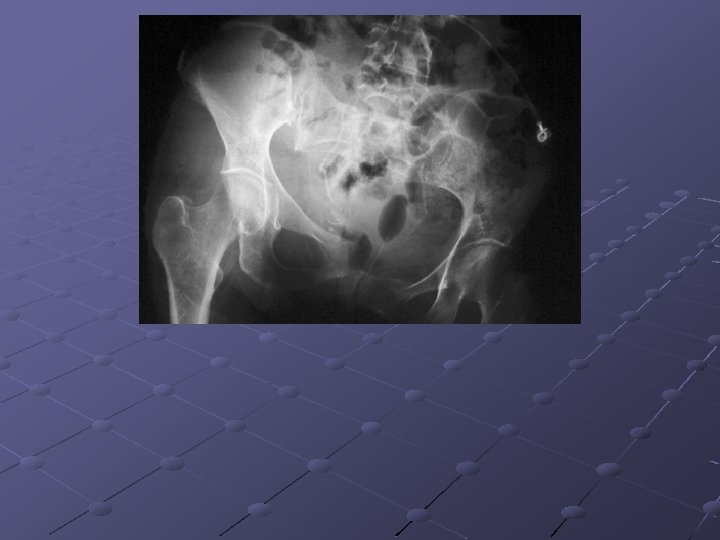

Imaging Studies